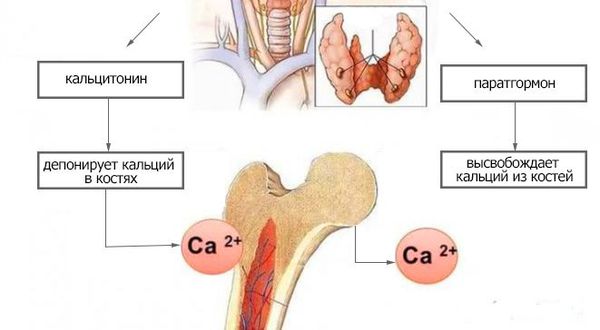

Иллюстрации и схемы по остеопорозу и паращитовидной железе